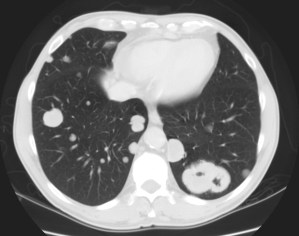

Las metástasis afectan el hígado, pulmones, glándulas adrenales, hueso, bazo, riñones y más raramente el peritoneo. Tumores metacrónicos del tracto superior se dan hasta en el 2-6% de las ocasiones. Una uro-Tc nos sirve para valorar al mismo tiempo la enfermdad metastásica y los tumores metacrónicos del tracto superior en los pacientes de cistectomizados de alto riespo.

Tras el tratamiento de la recidiva y nefrostomía para la hidroureteronefrosis, vuelve acudir al hospital a los 9 meses por episodio de dolor en FD y malestar general. Se realiza una ecografía de urgencias.

Se realiza nueva TC bifásico abdominopélvio y Uro TC.

- Paciente con numerosas recidivas por Cá vejiga.

- Ha desarrollado un tumor metacrónico en pelvis renal derecha, también responsable de la hidroureteronefrosis.

- Mala evolución radiológica del proceso a expensas de metástasis pulmonares y hepáticas.